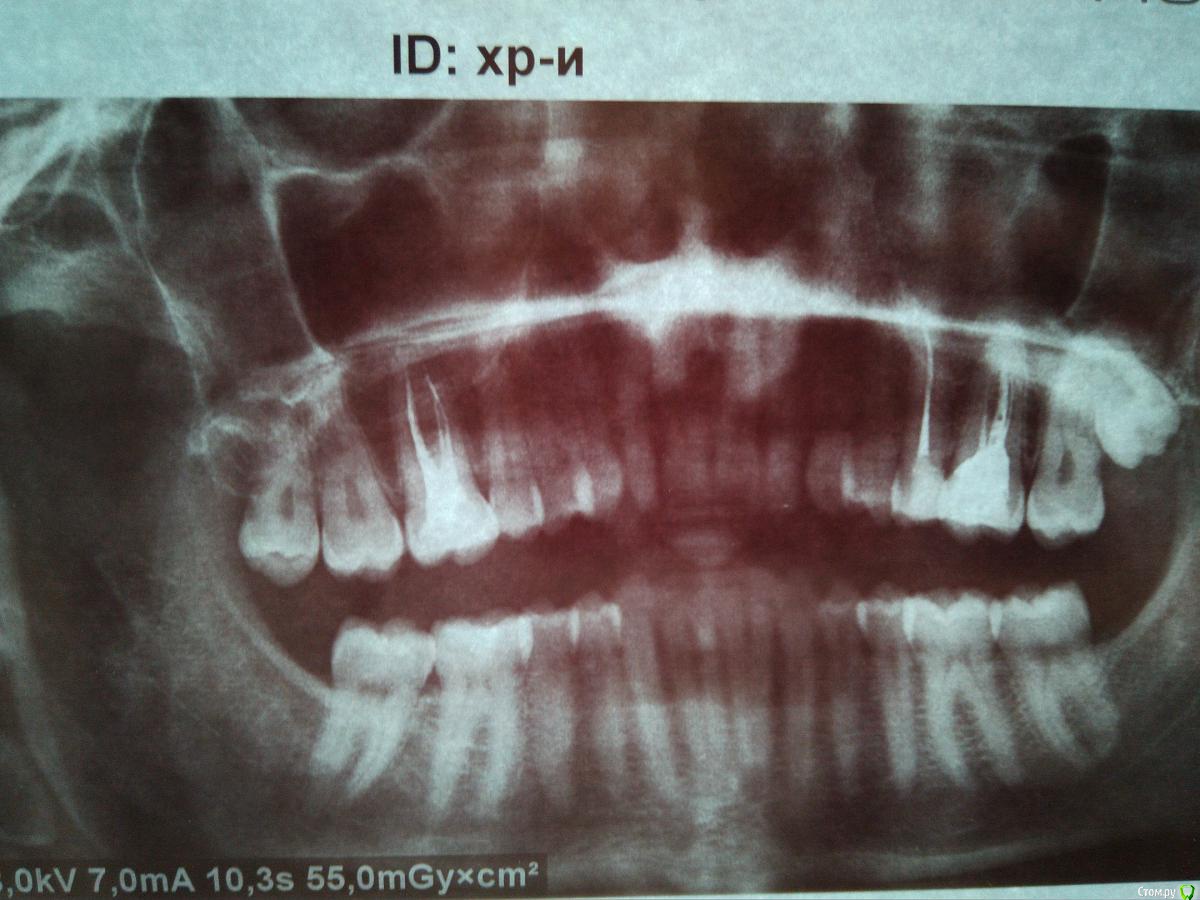

Dima87 Опубликовано 21 марта, 2018 Автор Поделиться Опубликовано 21 марта, 2018 (изменено) Уважаемые, с Вашего позволения подниму тему. Спустя 8 месяцев после пломбировки зуб все таки перестал щелкать. Сейчас, то есть спустя год после лечения, появились неприятные симптомы в области этого зуба при сильном сжимании челюсти и при жевании твердой пищи, а именно: периодически, но не всегда отдает в область носа, ощущается чувство давления в области корня зуба. В покое зуб не беспокоит. Понимая, что это нездоровые симптомы обратился к стоматологу в ведомственную поликлинику. Сделал ОПТГ по причине возникшей сложности сделать прицельный снимок зуба с учетом специфики местного визиографа - на снимок не попадал самый длинный корень зуба. Стоматолог не увидел проблем, сославшись на то, что корень зуба находится в в/ч пазухе и все описанные мною симптомы это норма. С декабря месяца 3 раза переболел ОРЗ (ОРВИ?), хотя на протяжении 20 лет болел 1 раз в год, а то и реже, появился хронический тонзиллит со стеканием слизи в носоглотку, что дало повод обратиться к отоларингологу. Сделав RG пазух носа была выявлена киста в альвеолярной бухте в/ч пазухи. 20.03 сделал МСКТ придаточных пазух носа. В заключении - КТ признаки кисты (одонтогенной?) правой верхнечелюстной пазухи, в области верхушки небного корня 16 зуба с запломбированным каналом выявляется мелкая киста-гранулема размером 9х13х13мм, плотностью до 21едН. Признаков деструкции костных стенок не наблюдается.Прикладываю прицельные снимки после пломбировки каналов зуба годовалой давности и свежий ОТПГ снимок.В моем понимании именно зуб послужил причиной возникновения кисты в пазухе. Требуется ли дентальное КТ для подтверждения одонтогенного происхождения кисты. Посоветуйте, пожалуйста, что делать с этим зубом. Изменено 21 марта, 2018 пользователем Dima87 Ссылка на комментарий